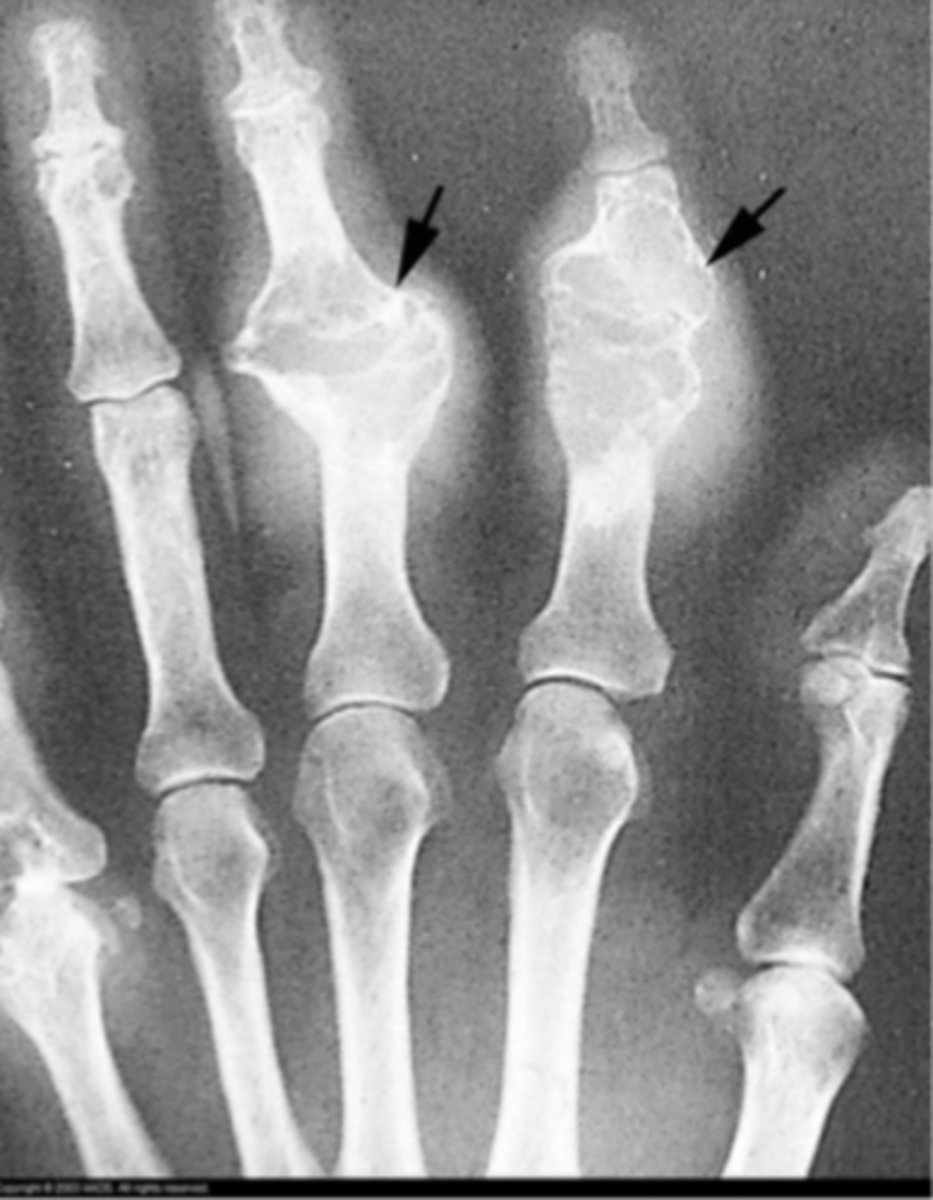

gout

What is the issue?

rheumatoid arthritis